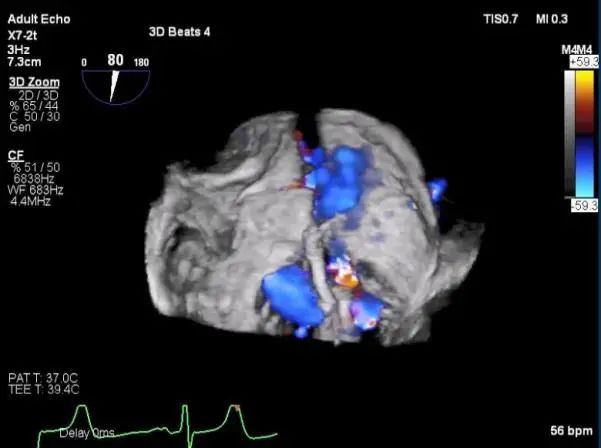

三维超声心动图显示第一枚XTR夹子释放,残余返流主要位于外侧

引导第二枚XTR夹子转向外侧残余病变区域并逐渐进入左室

第二枚XTR夹子释放,返流明显减少

三维超声心动图显示第二枚XTR夹子释放